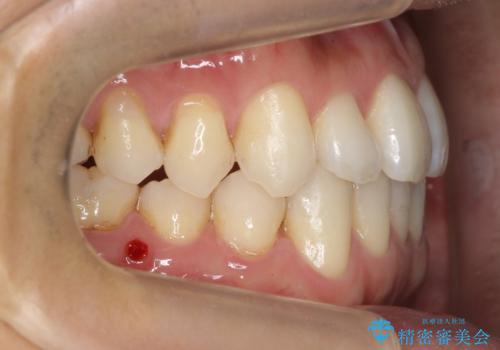

引っ込んでいる前歯の前方に下の犬歯が深く咬み込んでおり、また、奥歯のかみ合わせも受け口方向にずれ、骨格性の反対咬合も少々ありました。

上の前歯を前方に出すだけでは治療ができないため、ミニスクリューを用いて下の奥歯を後ろに送っています。